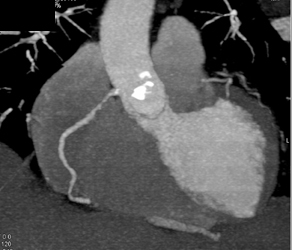

Normal RCA